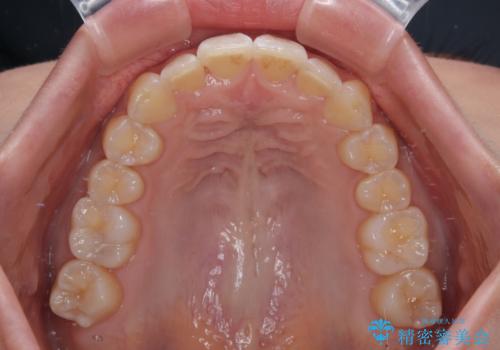

前に飛び出して目立っている前歯を整える インビザライン矯正治療

- 前方に主張した前歯2本を気にして来院された患者様です。

下顎前歯がデコボコしており、その影響で上顎前歯が前方に押し出されている状態でした。

口元が閉じにくいという印象はなかったため、非抜歯矯正にて歯列を整えていくこととしました。

上下左右の親知らずを抜歯し、上下ともに歯列を後方と側方に拡大し、口元を突出させることなくデコボコを解消することとしました。